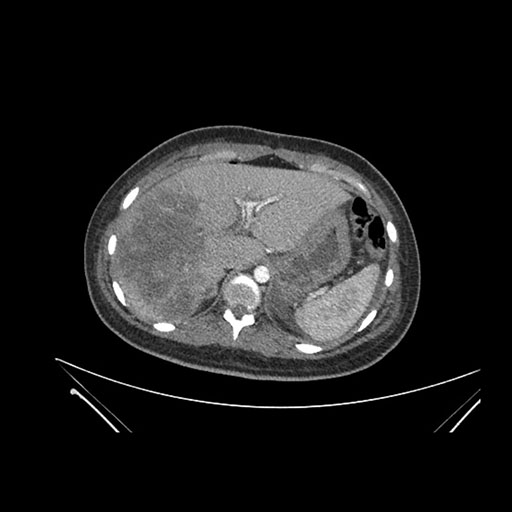

Imaging Analysis

Look through the patient's CT scan to identify any areas of concern for the necessary procedure.

Axial Arterial

Based on initial findings, which issue(s) would you be most concerned about?